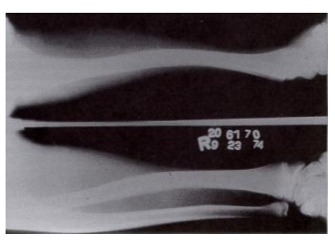

if bone is bent, which side will break first

the side experiencing tensile forces, NOT the compressed side

butterfly fragment is always located on the (tension//compression) side of bone

compression